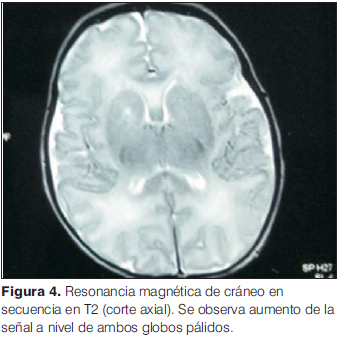

Se solicita resonancia magnética de cráneo a los 14 días de vida que informa a nivel de ambos globos pálidos y a nivel subtalámico un aumento de la señal en T1 y T2 (figuras 3 y 4).

Las manifestaciones clínicas de encefalopatía por bilirrubina incluyen diversos grados de compromiso neurológico. La fase aguda se caracteriza por rechazo del alimento, letargia, alteraciones del tono muscular (hipo/hipertonía), opistótonos(9). La fase crónica se caracteriza en los primeros meses de vida por hipotonía, persistencia de reflejo tónico asimétrico y retraso motor, sordera y parálisis de la mirada. La alteración extrapiramidal aparece luego de los 6 meses de vida, en la mayoría luego del primer o segundo año y se caracteriza por parálisis cerebral de tipo disquinética (ya sea distónica y/o coreoatetósica). El nivel intelectual se afecta en 25% de los pacientes. Con la aparición de la resonancia magnética (RM), las lesiones cerebrales propias de este síndrome se han identificado y descrito en neonatos a término. Existe una secuencia cronológica de las lesiones del kernicterus detectables por RM craneal. En una primera fase (fase aguda) se puede detectar un incremento de señal en secuencias T1 en los núcleos pálidos y en ocasiones en núcleos subtalámicos. Estas alteraciones han sido ya descritas en neonatos pretérmino o a término hiperbilirrubinémicos con 5 días de vida. En una segunda fase (transicional), se produce una atenuación de la hiperseñal en T1 a lo largo de las 2-3 semanas de vida hasta normalizarse. Finalmente, en una tercera etapa (fase crónica) se produce un aumento de señal en T2(9). Sin embargo, estas áreas anormales de alta intensidad no pueden ser observadas después de 1 año de edad, y son a veces sutiles y fácilmente pasadas por alto(11).

En el paciente del caso clínico presentado clínicamente se observa hipotonía axial (fase aguda) que junto al resultado de la RM de aumento de la señal en T1 y T2 en ambos globos pálidos y a nivel subtalámico orientan al diagnóstico de encefalopatía aguda por bilirrubina (figuras 1 y 2). En este caso clínico se identifican como factores de riesgo de ictericia: sexo masculino, 37 semanas de edad gestacional, pérdida de peso mayor de 10%, e ictericia visible antes del egreso. Destacamos en nuestro paciente, además, otros factores que favorecen niveles altos de bilirrubina luego del alta como son alta hospitalaria antes de las 72 h de vida y la alimentación basada en pecho directo exclusivo.